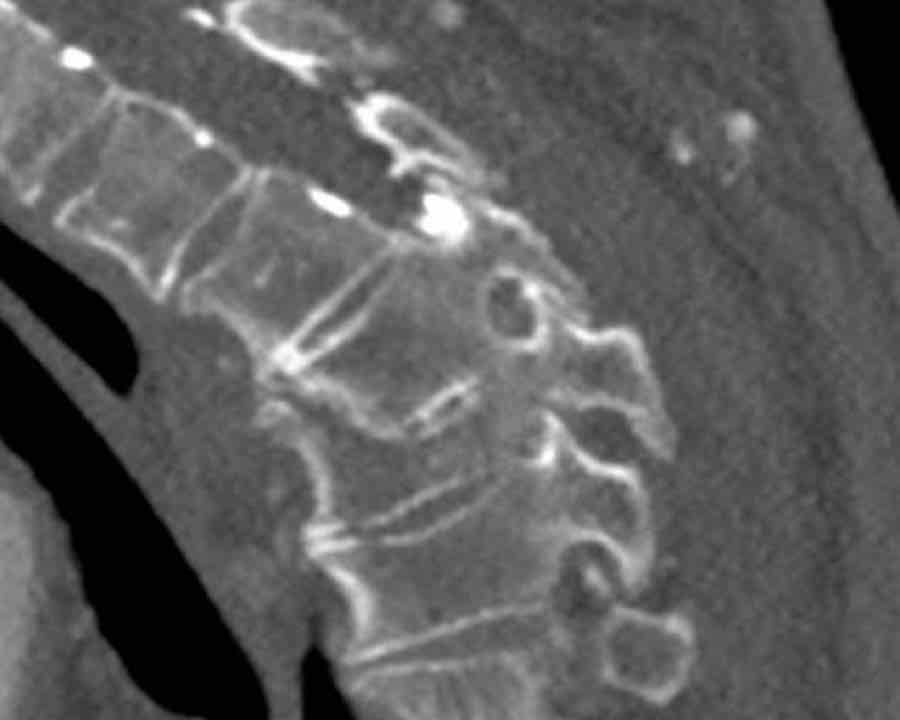

Scroll through the images

Findings:

- Perched facet joints (yellow curved arrows), so think of C injury.

- Posterior displacement of the vertebral bodies in the midline.

- Secondary A4 injury of the vertebral body.

Conclusion

Type C + A4 injury